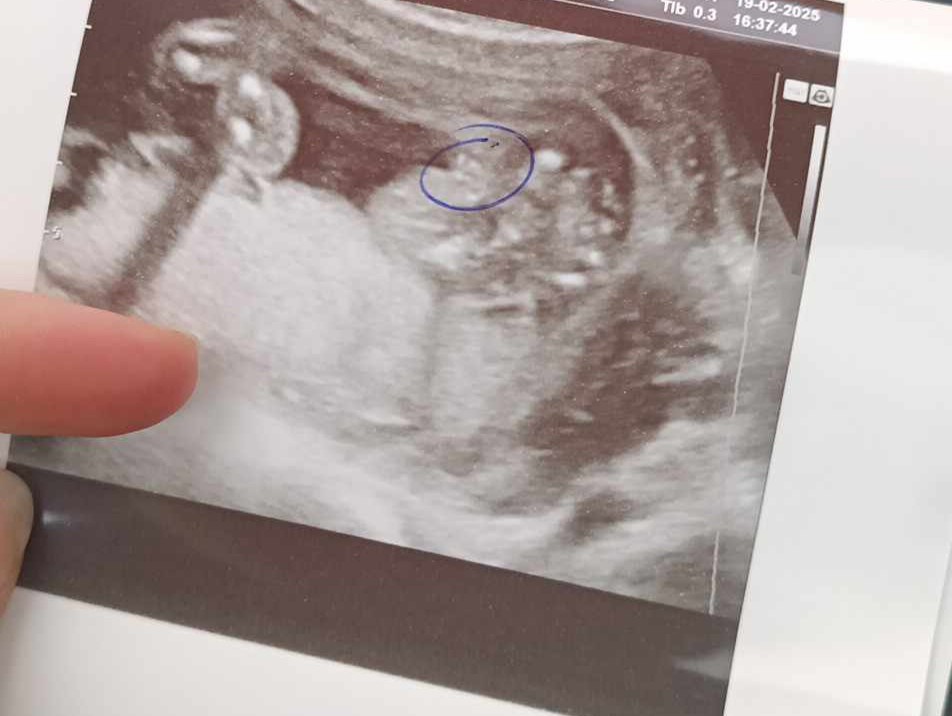

Hej , byłam dziś na badaniu połówkowym, badanie masakra nic się nie dowiedziałam tylko to ile waży maleństwo i to że to chłopiec ?!

Posiadam również dwa zdjęcia USG ... Cały dzień dziś mam mętlik w głowie i nie wiem co myśleć ...

Wrzucam zdjęcia z poprzednich USG